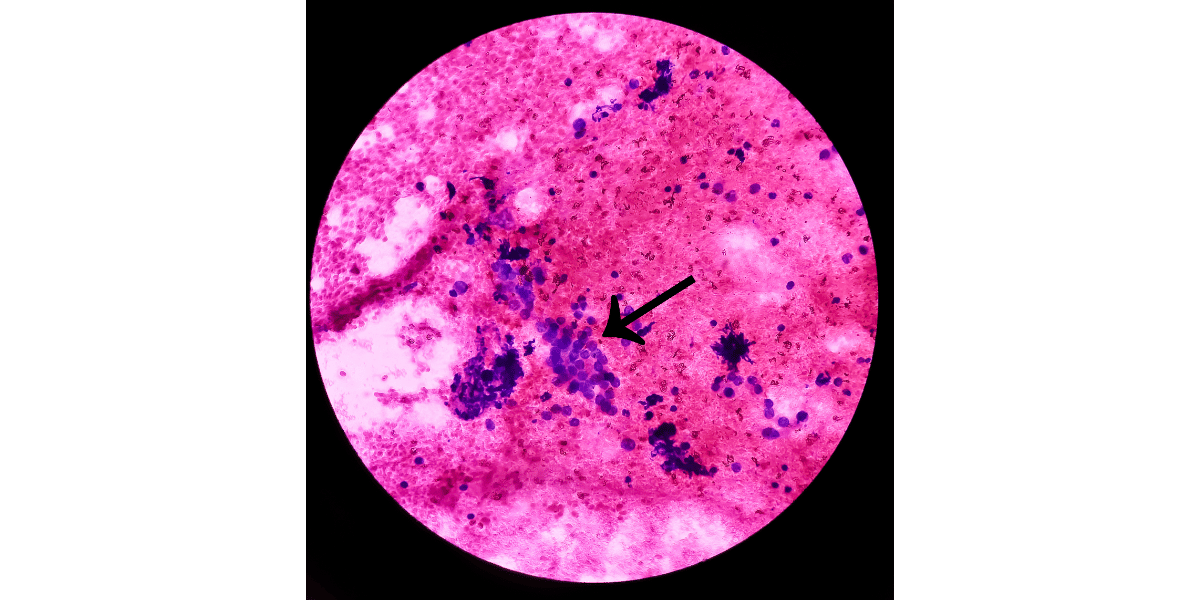

- Une biopsie consiste à prélever un échantillon de tissu pour examen microscopique.

- La biopsie peut être réalisée pour confirmer le diagnostic d'histiocytofibrome et exclure d'autres conditions plus graves type lentigo solaire, prolifération de mélanocytes, nævus, mélanome, etc.

- Une biopsie peut être recommandée si la lésion est atypique, si elle a changé de manière significative, ou si le médecin a des doutes quant à sa nature.